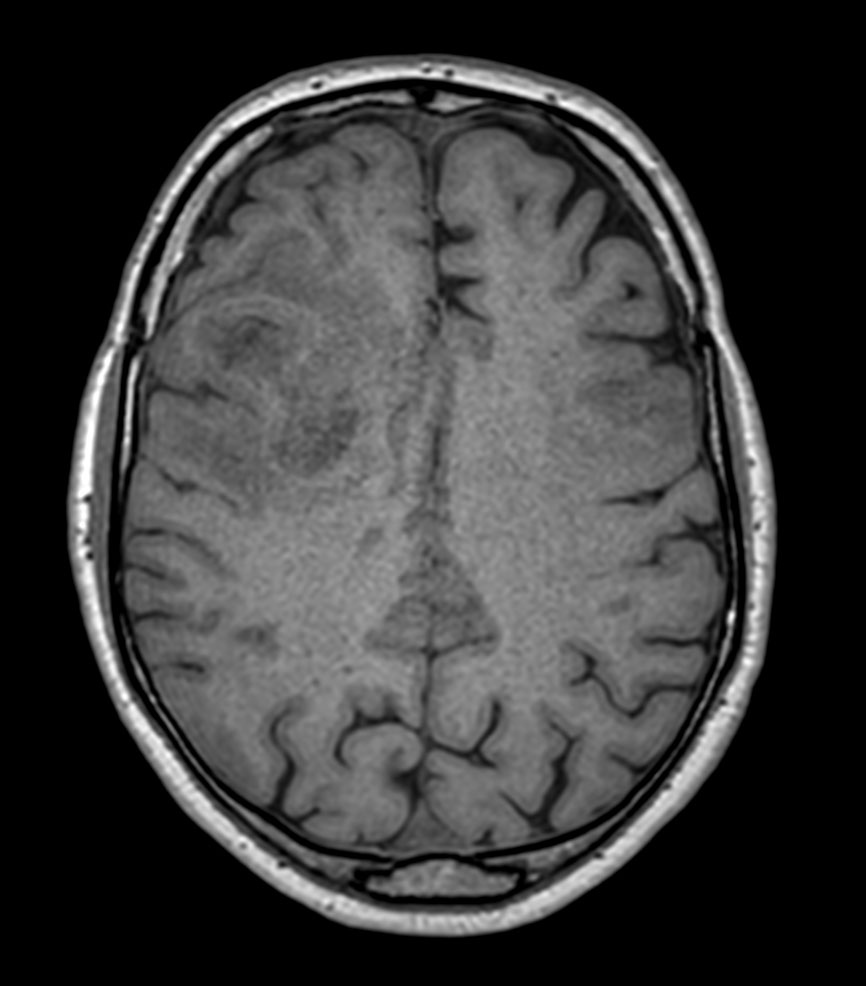

Patient with a revasculerized area with small bleedings. Diagnosed as malignant glioblastoom.

Axial 3D T1w TFE

Axial 3D T1w TFE with gado